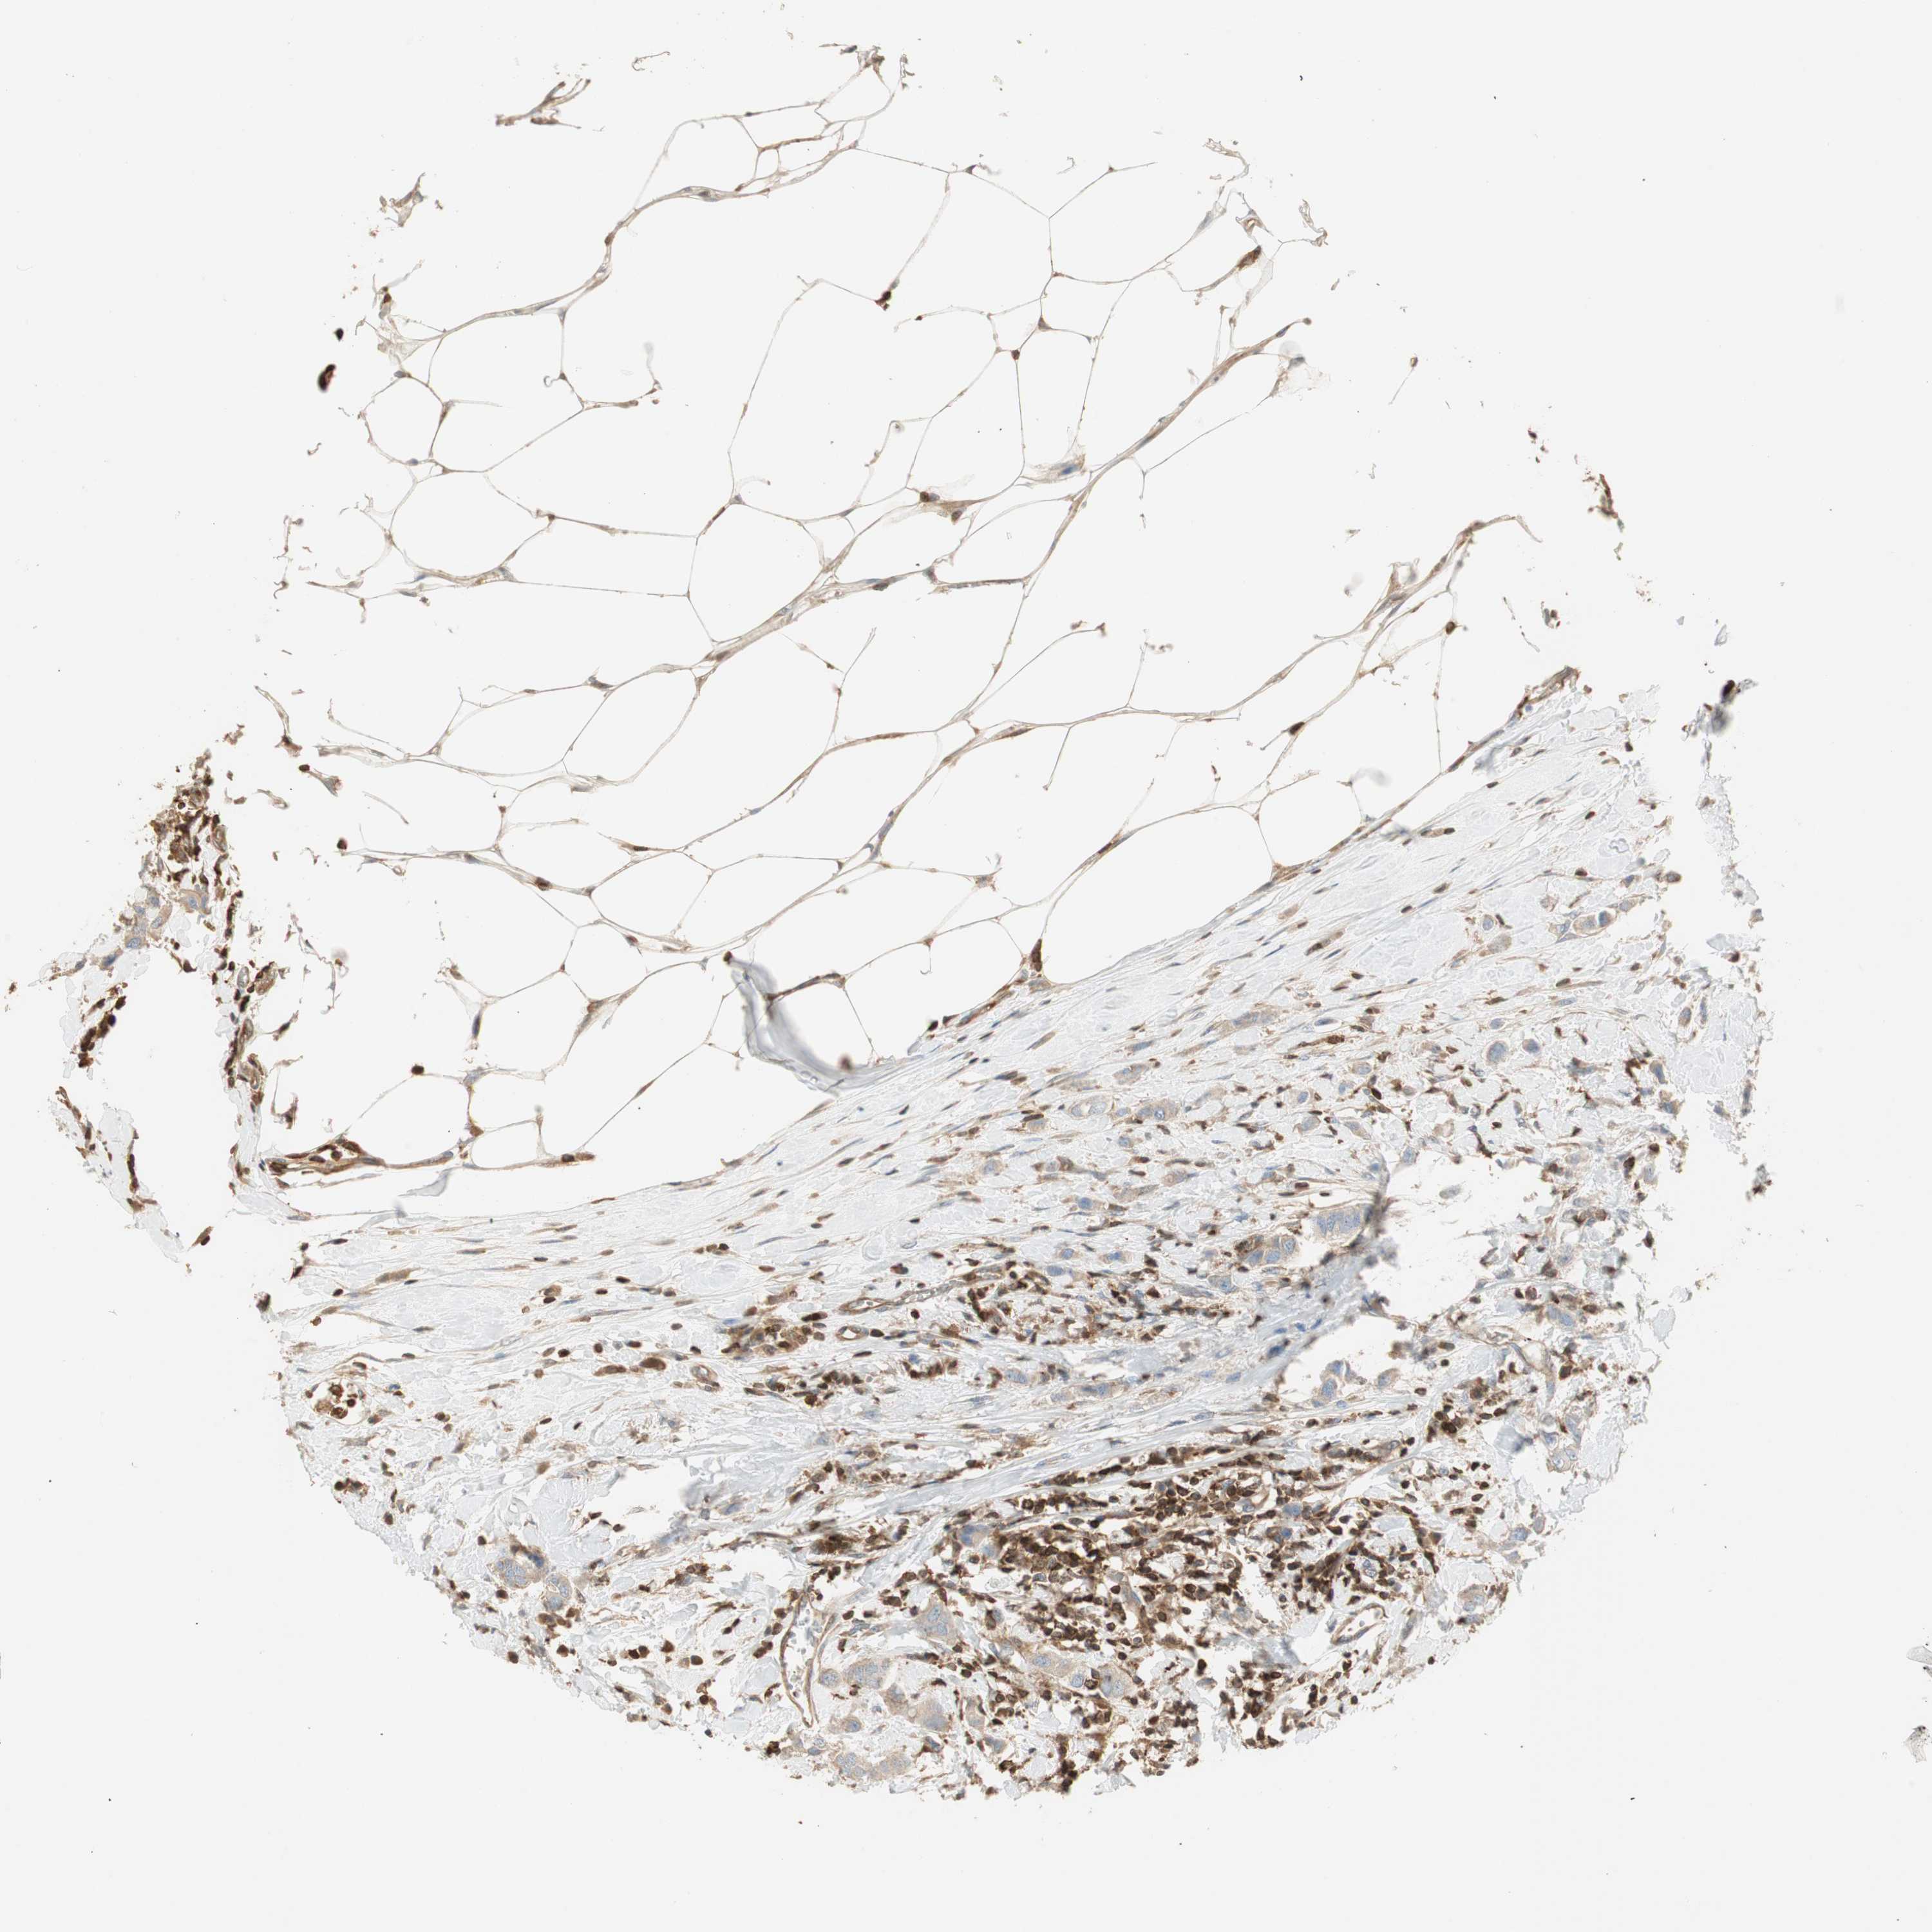

BRCA TCGA BRCA VALIDATION PROTEIN EXPRESSION